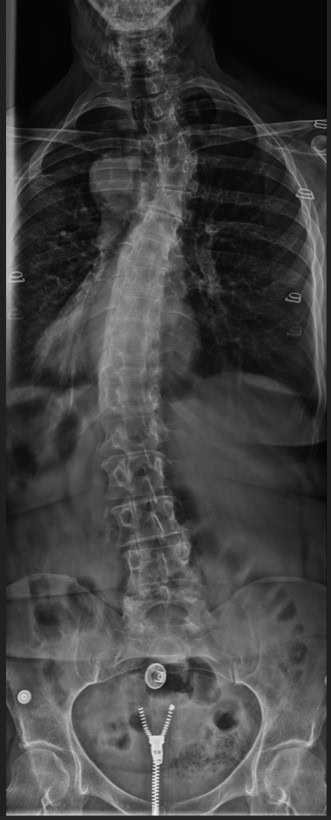

Pre Scan